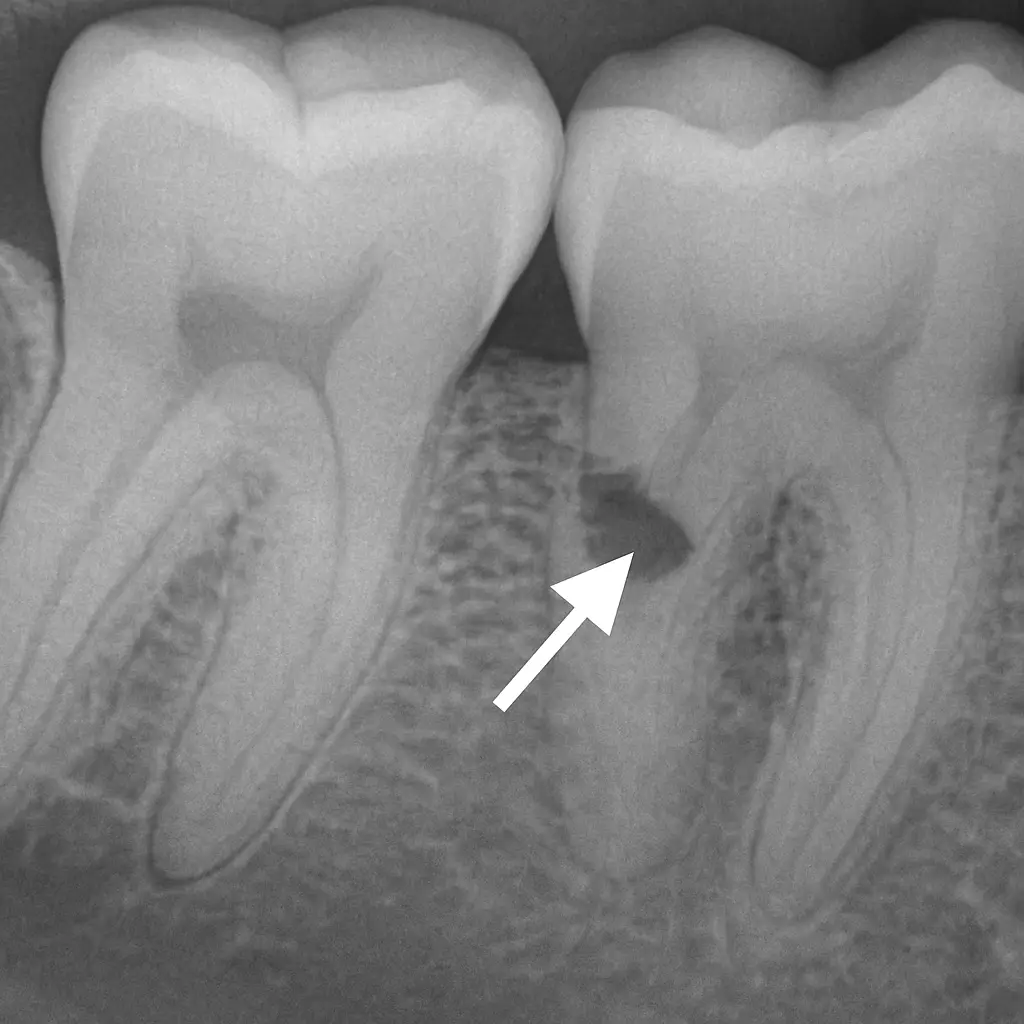

Along with a trained eye, one of the most essential tools for detecting cavities is still the x-ray. X-rays help us see what’s happening in the tight spaces between your teeth where decay can often hide. But by the time a cavity shows up clearly on an x-ray or during a visual exam, it’s usually already progressed.

That’s why early detection matters. The earlier we catch a cavity, the simpler and less expensive the treatment. Small spots of decay can often be treated quickly and painlessly, before they cause real damage.